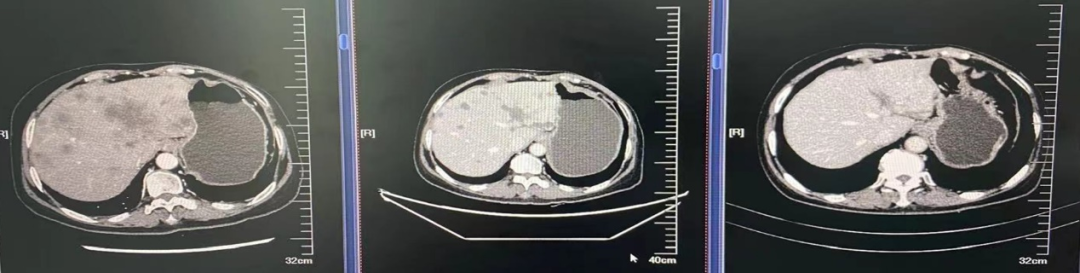

图6

图7

图8

图9

图10

图11